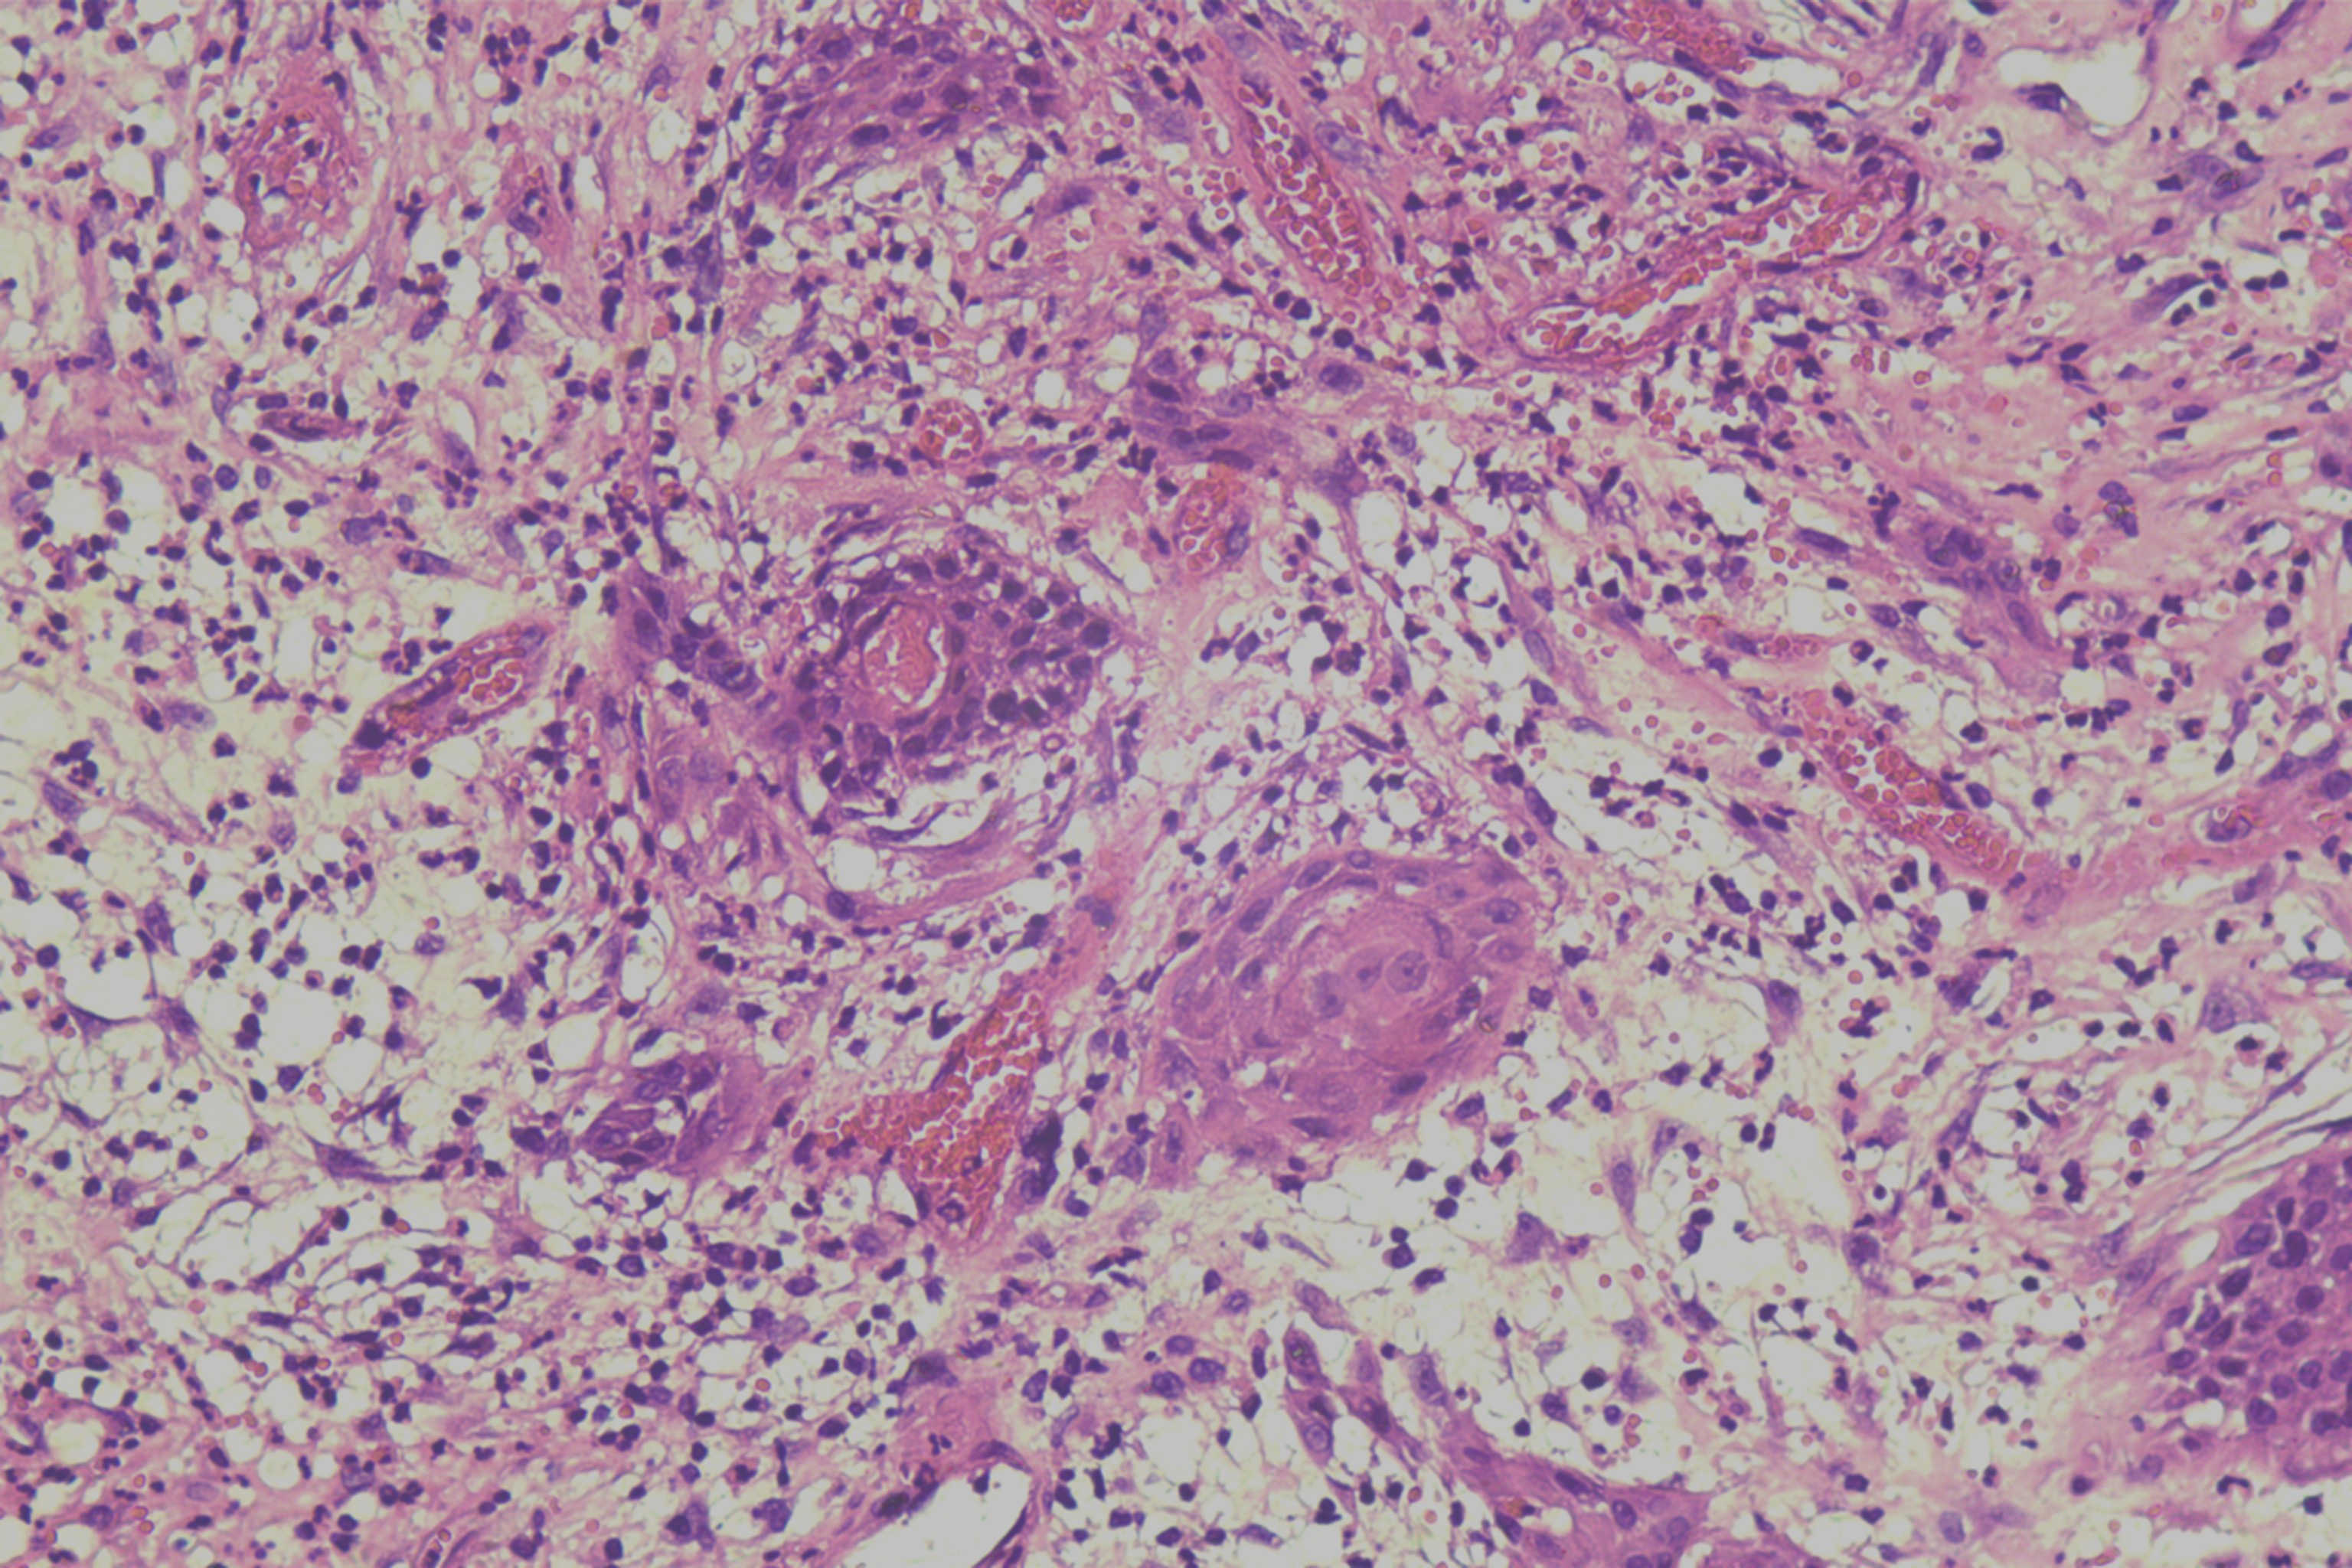

鳞癌?

性别

男

年龄

68岁

头皮肿物20年,包块逐渐增大,反复破溃

头皮肿物(局部活检)

1.5*1*0.3cm灰红碎组织一堆

考虑:基底细胞癌